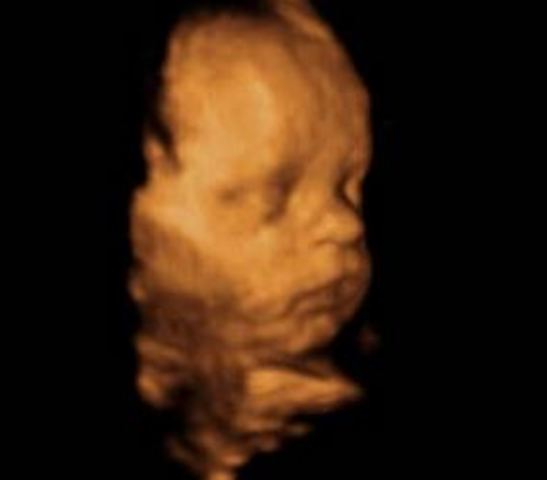

• Semana 14

Semana 14

Las orejas del feto se encuentran implantadas a ambos lados de la cabeza y también los ojos se han acercado; tanto que ya se distingue el puente de la nariz.

- Su cabeza sigue siendo mucho más grande en proporción con su cuerpo.

- Su hígado es aún muy grande, porque tiene que fabricar células sanguíneas

- Su piel sigue siendo tan sumamente fina que a través de ella se pueden ver algunos de los órganos internos y los vasos sanguíneos.